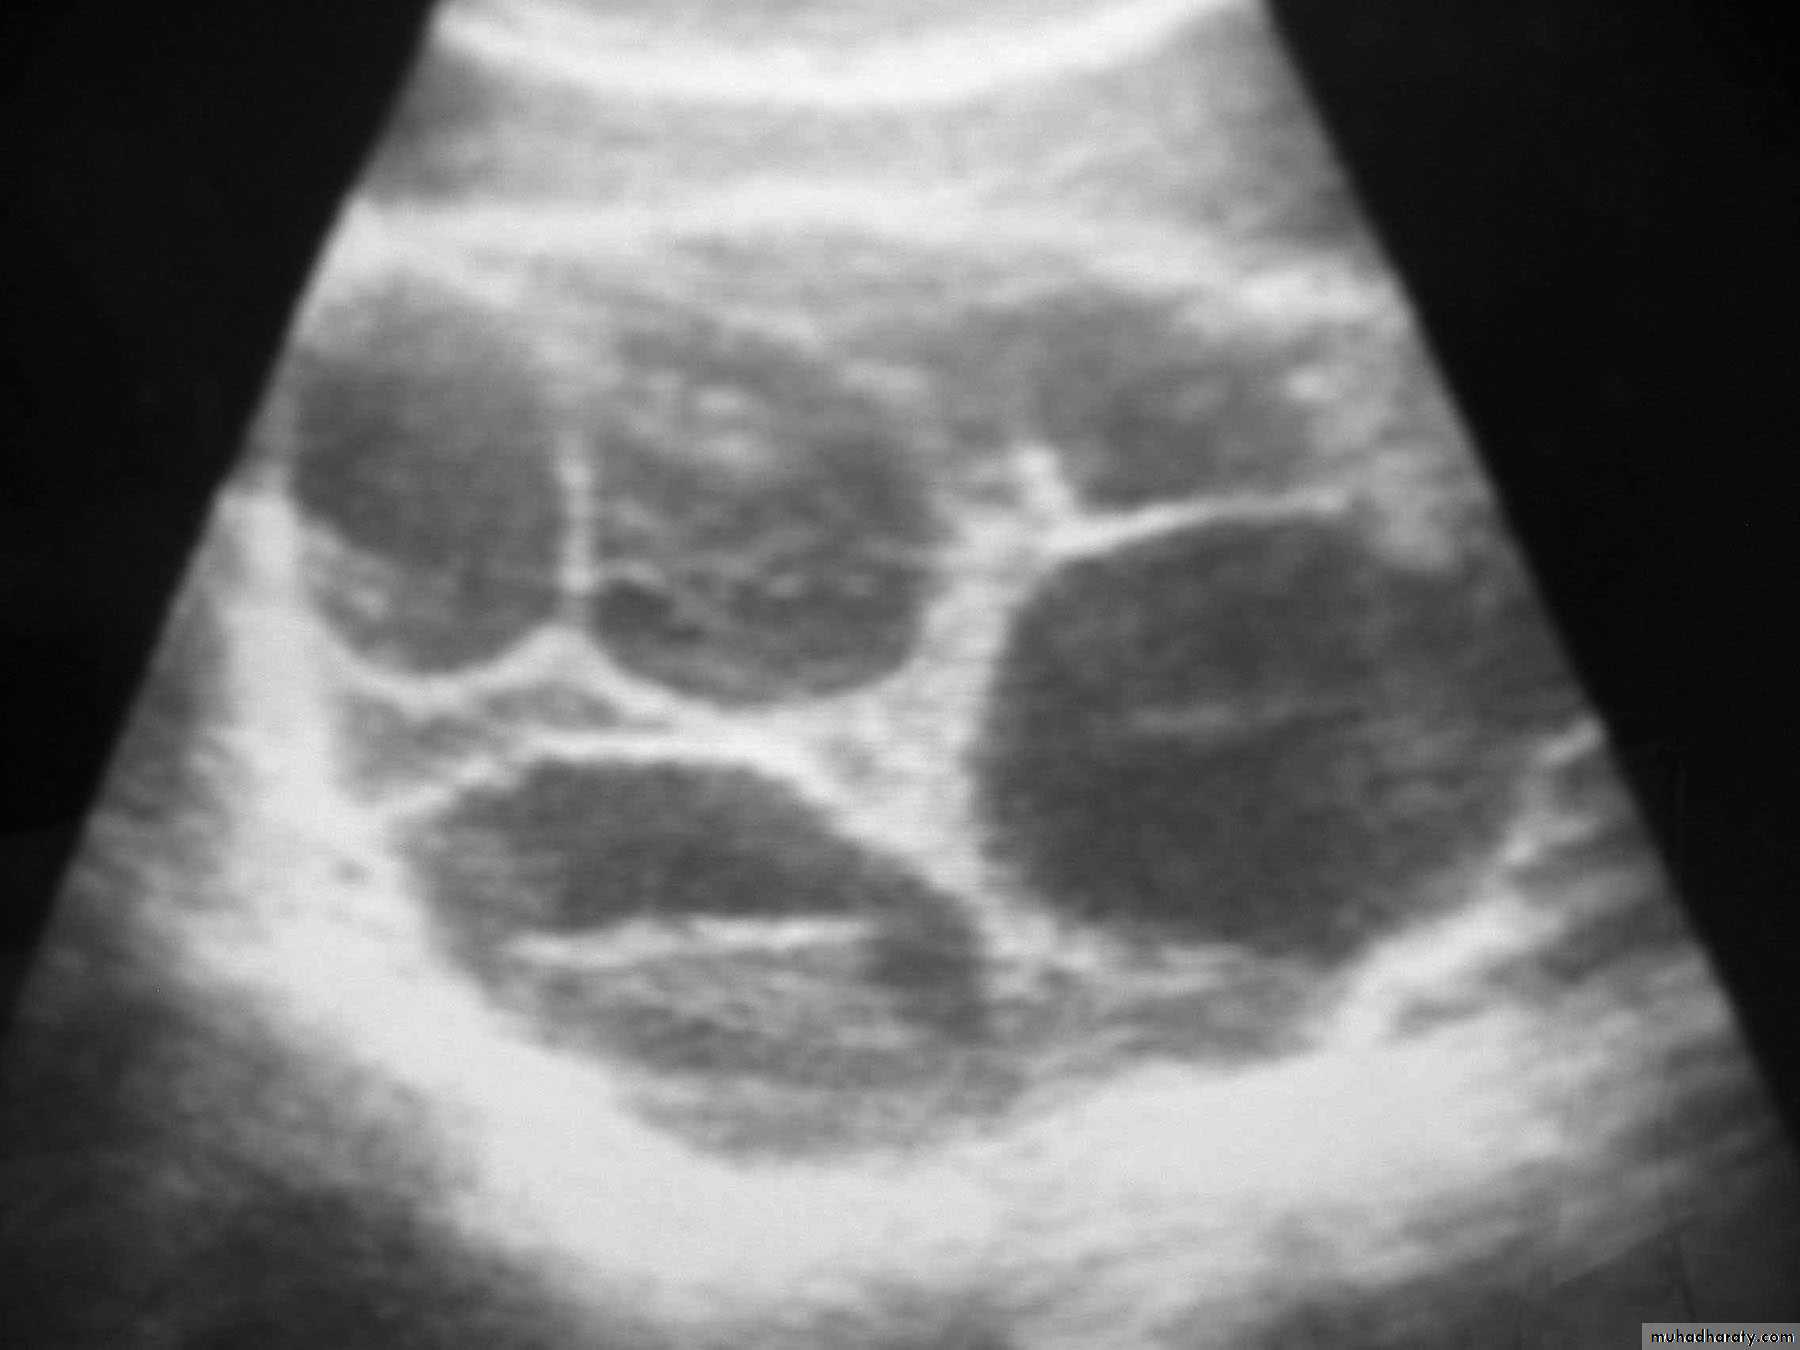

ultrasound:

a. which confirm diagnosis of mole as show snowstorm appearance (uterine cavity filled with multiple sonolucent area of varying size and shape).

b. absence of fetus.

Theca Lutein cyst of ovary.